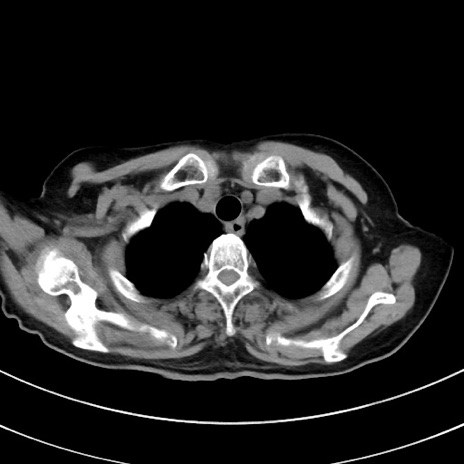

症例33(横断像)

【症例】70歳代 女性

【主訴】心窩部痛

【現病歴】延髄病変の精査・加療にて神経内科入院中。本日より心窩部痛あり。

【既往歴】虫垂炎

【身体所見】右下腹部を中心に圧痛と反跳痛あり。

【データ】WBC 10900、CRP 0.02